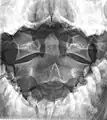

![]() Second cervical vertebra, or epistropheus, from above | |

Axis seen from above